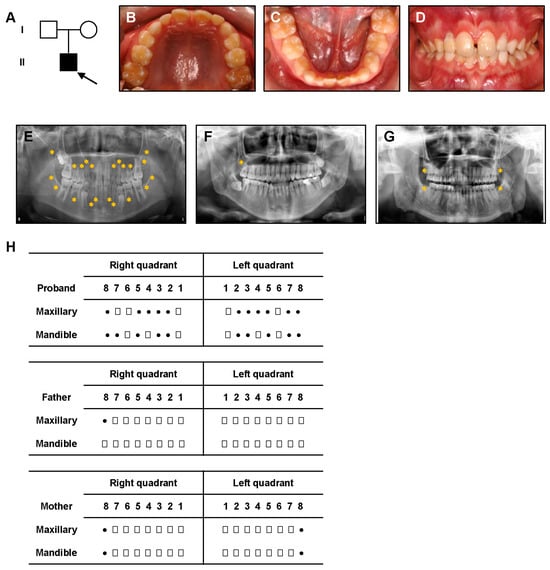

Identification of a Novel EVC2 Variant in a Family with Non-Syndromic Tooth Agenesis and Its Potential Functional Implications

by Changqing Yan, Jie Li, Chenying Zhang, Yang Liu, Xiaozhe Wang and Shuguo Zheng

Genes 2025, 16(11), 1288; https://doi.org/10.3390/genes16111288 - 30 Oct 2025

Viewed by 573

Abstract

Background/Objectives: Non-syndromic tooth agenesis (NSTA) is a congenital condition that causes the absence of one or more teeth without accompanying systemic abnormalities, which significantly affects quality of life. Genetic factors, including mutations in several specific genes, contribute to the pathogenesis of NSTA. [...] Read more.

Background/Objectives: Non-syndromic tooth agenesis (NSTA) is a congenital condition that causes the absence of one or more teeth without accompanying systemic abnormalities, which significantly affects quality of life. Genetic factors, including mutations in several specific genes, contribute to the pathogenesis of NSTA. This study investigates a novel EVC2 mutation in a patient with NSTA and explores its potential pathogenic mechanism, with the aim of enriching the spectrum of pathogenic genes. Methods: Whole-exome sequencing (WES) was performed on peripheral blood samples from a patient diagnosed with NSTA. Bioinformatics analysis was utilized to identify the mutation and assess its potential impact on protein structure and function. Molecular dynamics simulations were conducted to analyze structural alterations in the EVC2 protein. The binding affinity between EVC2, EVC, and Smoothened (SMO) was to determine the effect of mutation on protein–protein interaction. Protein localization and expression were analyzed using immunofluorescence and Western blotting. Reverse transcription quantitative PCR (RT-qPCR) was employed to evaluate downstream signaling pathway alterations. Results: A novel EVC2 mutation (c.1657_1660delinsA, p.Glu553_leu554delinsMet) was identified in the proband, and the mutation was maternally inherited. Molecular dynamics simulations revealed that the mutation resulted in a decrease in α-helical content and significant conformational changes in the protein structure. This led to reduced binding affinity between EVC2 and its ligands EVC and SMO, destabilizing the structural integrity of the protein complex. Despite these structural changes, EVC2 protein localization and expression were unaffected. Furthermore, a downregulation of GLI1 and SHH expression was observed, indicating impaired Hedgehog (Hh) signaling. The downregulation of the Hh signaling pathway impairs the tooth development process and may lead to the occurrence of tooth agenesis. Conclusions: A novel EVC2 mutation was identified in a patient with NSTA. Based on molecular dynamics simulations, it is hypothesized that this EVC2 variant could contribute to the pathogenesis of NSTA by impairing the EVC2-EVC-SMO complex formation, which may lead to downregulation of downstream GLI1 and SHH. These findings provide new insights into the molecular mechanisms underlying EVC2-mediated NSTA, suggesting that disruption of Hh signaling may represent a critical pathogenic mechanism. Full article

Show Figures

Figure 1